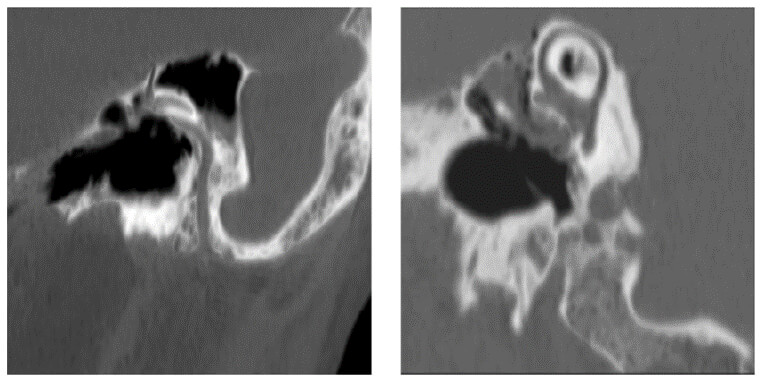

Inner Ear

On these images, we can see an example of how the minimum intensity projection is used in the diagnosis of the semicircular canal. Abnormalities such as cholesteatomas can be easily seen.